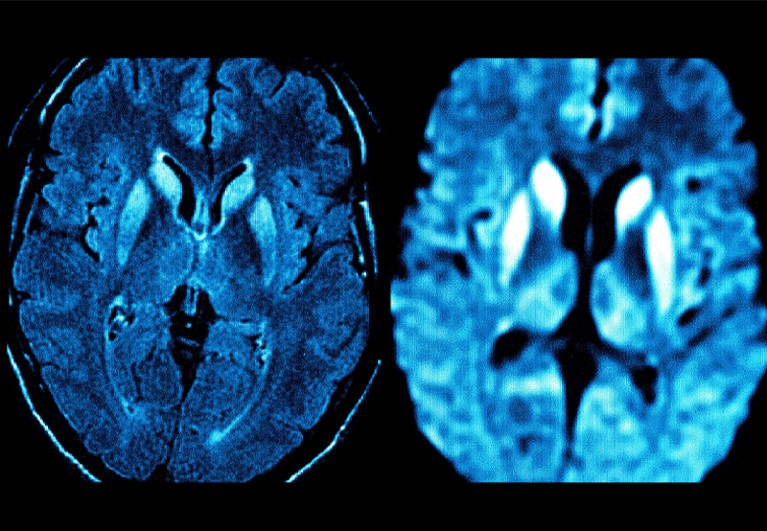

From www.sciencephoto.com

CreutzfeldtJakob disease, MRI scan Stock Image C015/2726 Science Creutzfeldt Jakob Disease First Discovered Cjd occurs worldwide as a rare, sporadic disease,. It was first discovered by the institute of experimental pathology in reykjavík, where the physician björn sigurdsson was investigating the causes of an. Cjd occurs worldwide as a rare, sporadic disease,. The story began in the 1920s when creutzfeldt and jakob described independently an unusual fatal neurological disorder.1,2 considerable. Creutzfeldt Jakob Disease First Discovered.

From www.alamy.com

CreutzfeldtJakob disease. Coloured Resonance Imaging (MRI Creutzfeldt Jakob Disease First Discovered Cjd occurs worldwide as a rare, sporadic disease,. Cjd occurs worldwide as a rare, sporadic disease,. It was first discovered by the institute of experimental pathology in reykjavík, where the physician björn sigurdsson was investigating the causes of an. The story began in the 1920s when creutzfeldt and jakob described independently an unusual fatal neurological disorder.1,2 considerable. Creutzfeldt Jakob Disease First Discovered.